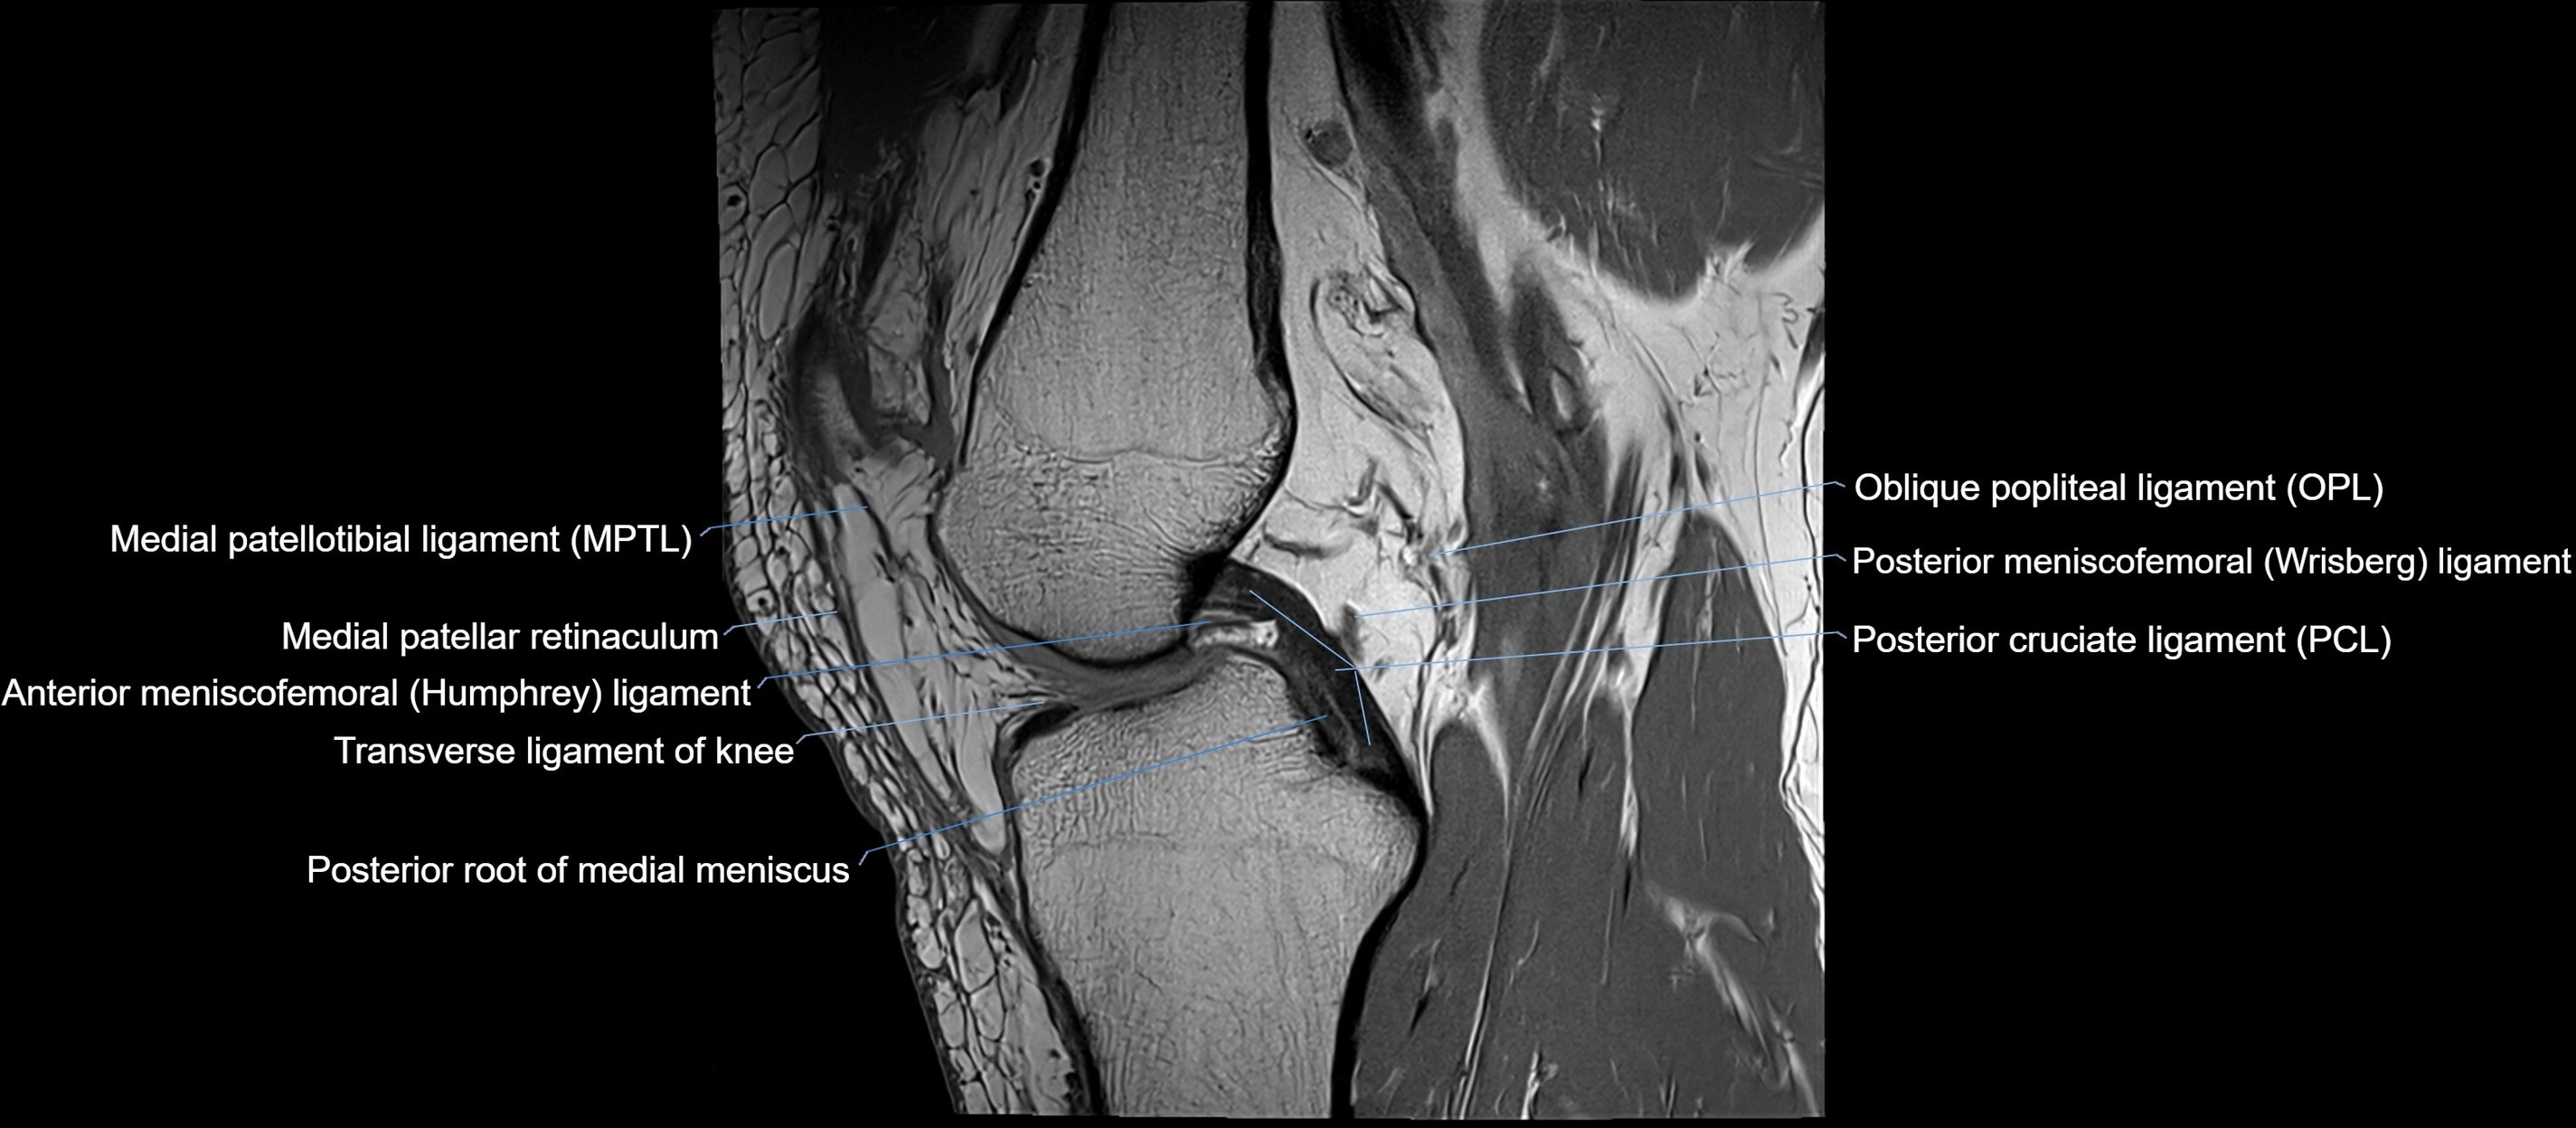

MRI images

image